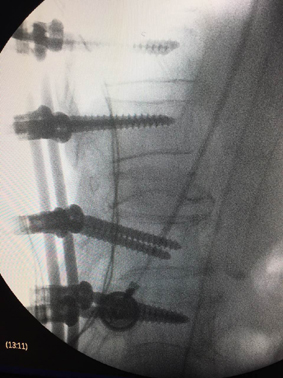

我院骨傷科又完成一例高難度脊柱后凸畸形經(jīng)椎弓根截骨矯形術(shù)

術(shù)后攝片

近日,我院骨傷學(xué)科主任、省中醫(yī)藥重點(diǎn)學(xué)科帶頭人陳建良主任醫(yī)師團(tuán)隊(duì)成功主持完成1例胸椎陳舊性骨折后凸畸形經(jīng)椎弓根截骨矯形術(shù),該手術(shù)的成功標(biāo)志著我院骨傷科脊柱矯形技術(shù)又上新臺(tái)階。

患者,蔣某,男性,74歲。因胸腰椎骨折5年多,且雙下肢進(jìn)行性神經(jīng)損傷2年,來(lái)我院診斷為胸椎陳舊性骨折后凸畸形伴脊髓馬尾神經(jīng)遲發(fā)損傷。因該患者病史長(zhǎng),手術(shù)神經(jīng)損傷風(fēng)險(xiǎn)高,骨傷科醫(yī)護(hù)團(tuán)隊(duì)經(jīng)過(guò)認(rèn)真術(shù)前準(zhǔn)備和討論,在手術(shù)麻醉科的大力支持配合下,經(jīng)過(guò)4小時(shí),順利完成手術(shù),目前患者術(shù)后神經(jīng)損傷恢復(fù)佳。

該項(xiàng)技術(shù)的開展得益于區(qū)衛(wèi)生計(jì)生局衛(wèi)生技術(shù)人才五年進(jìn)修培養(yǎng)計(jì)劃的實(shí)施,陳建良主任作為該項(xiàng)目培養(yǎng)衛(wèi)技人才,最近在浙醫(yī)二院專修脊柱外科,據(jù)他介紹脊柱畸形矯形術(shù)是高難度、高風(fēng)險(xiǎn)手術(shù),容易引起脊髓、馬尾神經(jīng)損傷,目前,該手術(shù)在縣市級(jí)醫(yī)院鮮有開展,乃大師級(jí)手術(shù)。